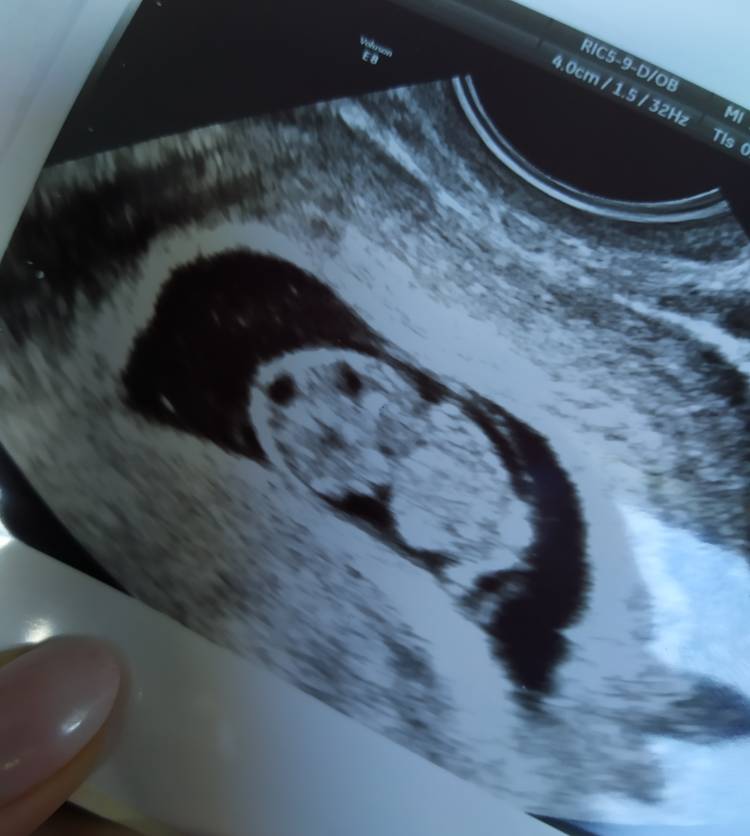

takie pamiątkowe zdjęcie dziś dostałam, wg USG 8+6, serduszko bije jak szalone pierwszy raz słuchałam aż się popłakałam [emoji24][emoji16] wszystko z nami ok rutynowe badanie przed 10tc

prawda że pięknie ? [emoji3059][emoji16]